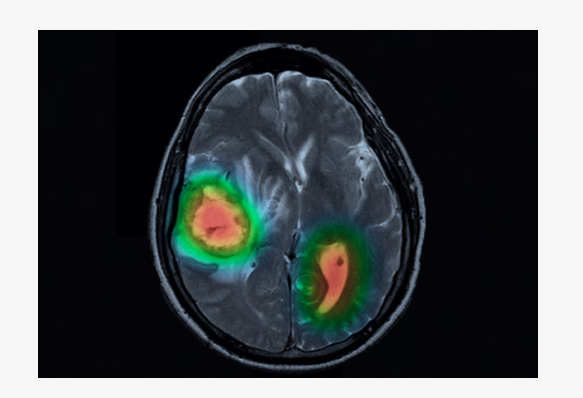

오토 딥러닝 알고리즘 기술은 이미지 기반 의료 연구에도 적용되고 있다. 컴퓨터단층촬영(CT), 자기공명영상(MRI), 엑스레이 등의 정상·병변을 바탕으로 딥러닝 모델을 구현해 병변을 신속·정확하게 검출할 수 있다. 의료진은 코딩 과정 없이도 뉴로클 SW를 사용해 대장 내시경 이미지에서 용종을 예측하고, 캡슐 내시경 영상에서 위장 병변을 분류했다.

이 대표는 “오토 딥러닝 알고리즘을 활용해 AI 전문가가 아닌 의료진도 원하는 병변 검출·분류 모델을 만들 수 있다”면서 “희귀질환이더라도 병원 진단 데이터를 바탕으로 딥러닝 모델을 생성해 의료진이 임상 연구에 활용하고 있다”고 설명했다.

뉴로클 제품은 병변 데이터가 부족해도 실제와 유사한 가상 병변 이미지를 생성하고, 소수 이미지만 라벨링 해도 자동으로 라벨링 영역을 추천하는 기능 등으로 의료진 사용 편의성을 높였다. 뉴로클 SW는 영상의학과, 소화기내과, 정형외과, 신경외과 등 다양한 진료과에 도입됐다.